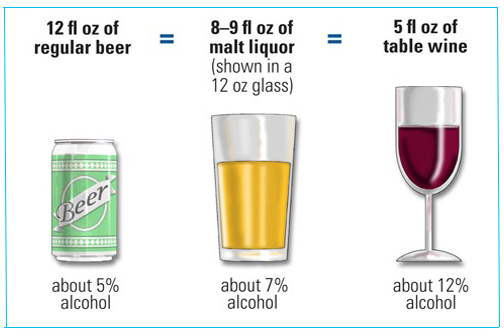

LSU Health New Orleans Study Suggests Interprofessional Team Training Could Prove Effective in AUD Prevention & Treatment

An LSU Health New Orleans study demonstrated the effectiveness of single, focused Interprofessional Education (IPE)-based exercises in preparing young health professions learners to limit or prevent alcohol use disorder (AUD). Students learned together as a foreshadowing of future interprofessional practice. This intervention produced significant decreases in the stigma associated with alcohol use, which is highly relevant for potential AUD patients. More